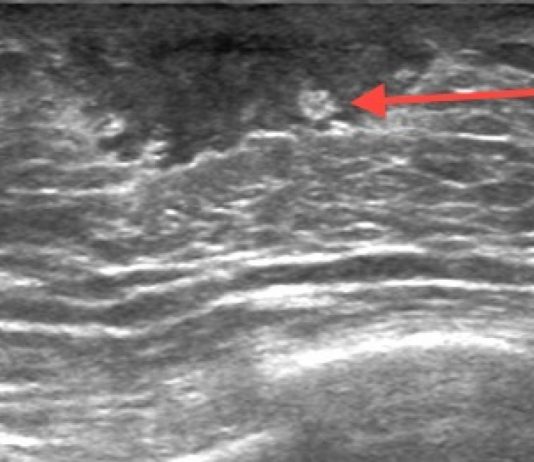

Внутрипротоковая папиллома

Внутрипротоковая папиллома, также известная как болезнь Минца, представляет собой папиллярное разрастание эпителия в просвете млечного протока.

Характерным симптомом заболевания являются спонтанные выделения из соска, которые...